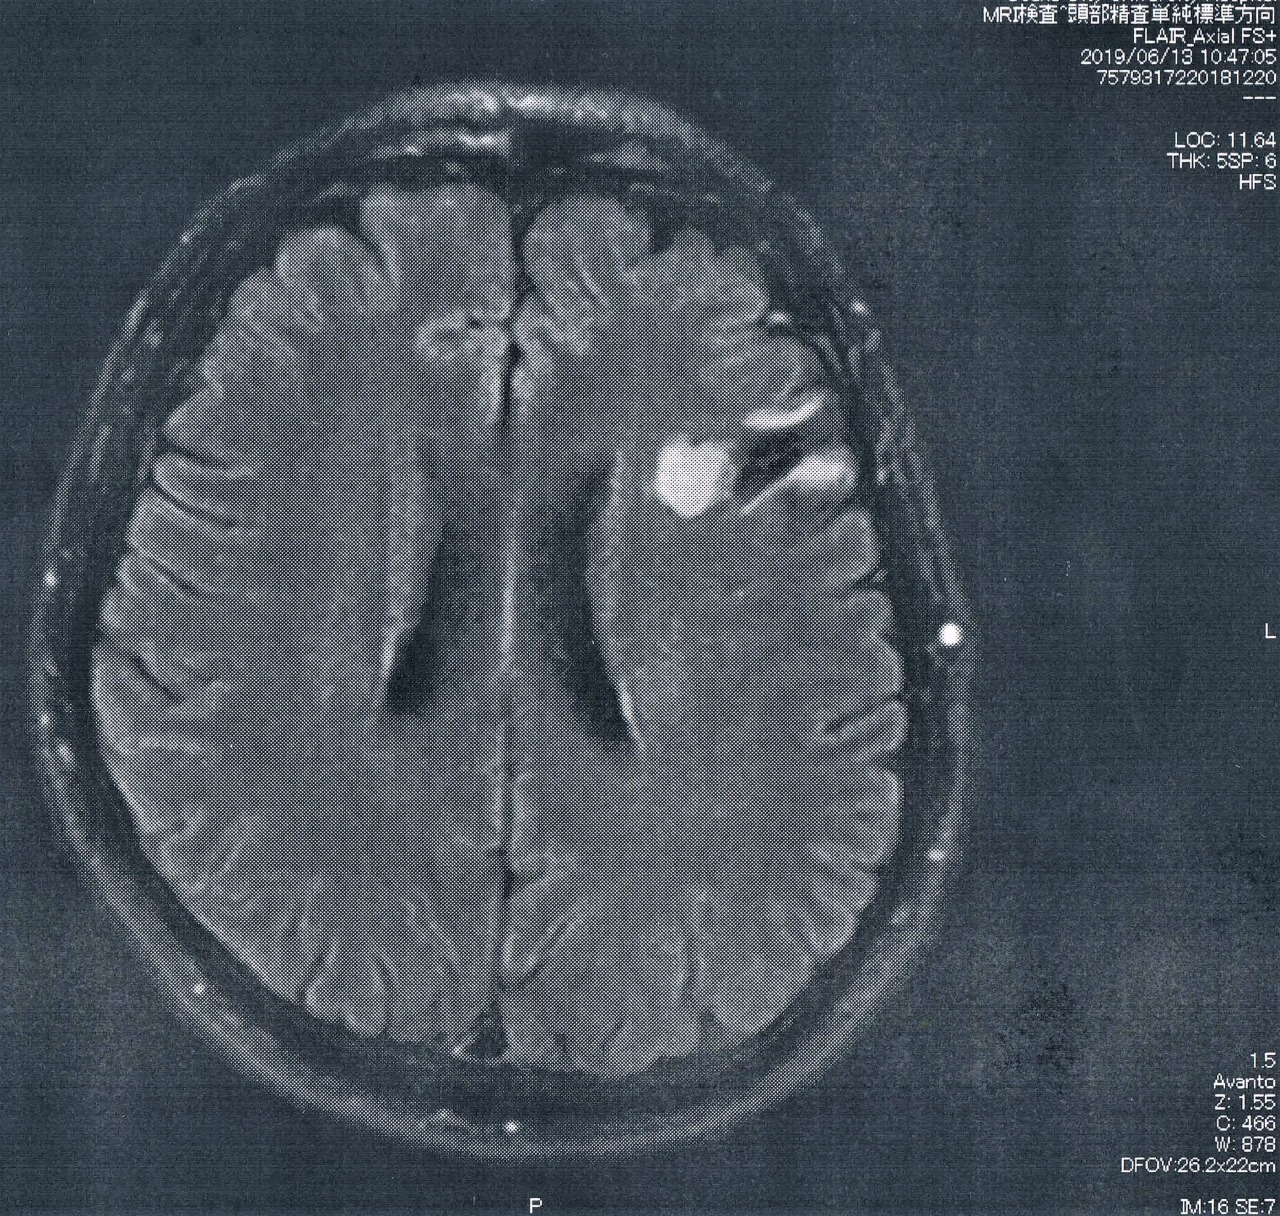

前回、造影剤を使ってMRI検査をして悪性転化がないことが確認されたので、今回は6か月おきの通常の定期検査。

特に変化はなく問題なしとのこと。

ただし、悪性転化しやすい腫瘍の種類(びまん性星細胞腫グレード2)であるとのことで、1年に一回は造影剤を注射してMRI検査をすることになった。なので、次回の検査は4時間前から絶食する必要がある。